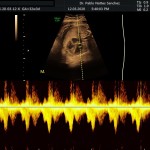

Modalidad de imagen ecográfica que permite evaluar flujos arteriales y venosos en estructuras fetales, placentarias y maternas obteniendo información valiosa sobre

- La oxigenación feto placentaria (bien estar fetal)

Este modo ecográfico nos brinda datos importantes desde la 6ta a la 40ta semana de embarazo. Nosotros la utilizamos en todos nuestros exámenes ecográficos.